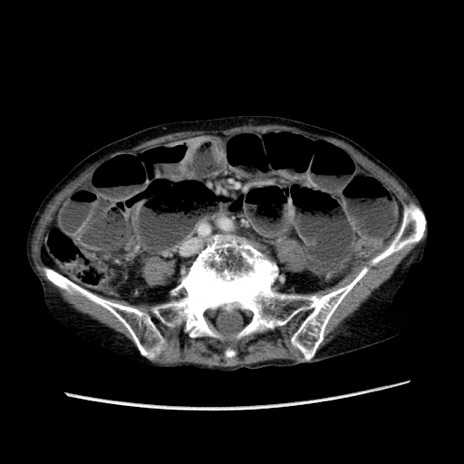

症例25(横断像)

【症例】80歳代女性

【主訴】胸のつかえ感

【現病歴】約9時間前に食後から胸のつかえた感じあり、嘔吐あり、来院。

【既往歴】胃癌(全摘)、胆摘、虫垂炎

【身体所見】心窩部に圧痛あり、反跳痛なし。

【データ】WBC 5700、CRP 0.05